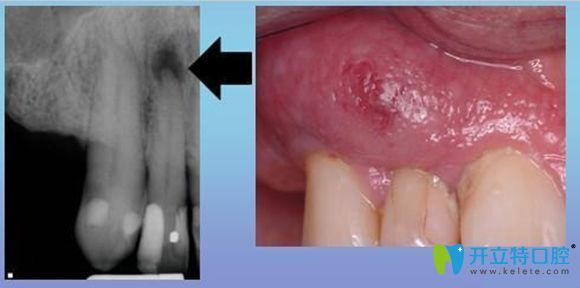

牙齦瘺管癥狀示意圖

牙齦瘺管它是一種常見的口腔疾病,其形成的原因很多,但是主要原因多是根尖周炎引起的。

它的臨床癥狀多表現(xiàn)為,患牙根部位置會先出現(xiàn)一個腫包,然后這個包會逐漸變大,并伴隨著分泌物溢出。

是因為急性根尖周炎癥形成膿腫,膿液引流不暢,往外排出導(dǎo)致的,也可以說是根尖周炎癥常見的一種排膿途徑。